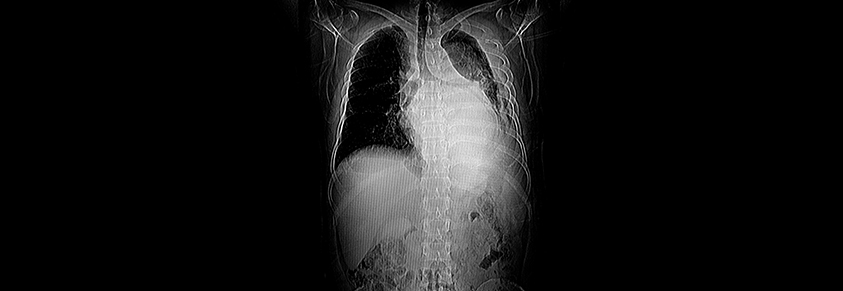

Die Computertomografie eines menschlichen Oberkörpers

Fettgewebe, Bauchspeicheldrüse und Leber untersucht

Computertomografie gibt Hinweise auf Diabetes Typ 2

Aufnahmen des Bauchraums mithilfe von Computertomografen (CT) werden aus verschiedensten Gründen angefertigt. Bestimmte Merkmale der Bilder geben einen Hinweis auf Diabetes Typ 2.